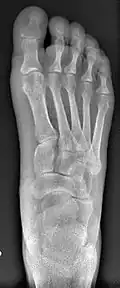

![]() Fig. 8a. Painful hallux valgus and metatarsus primus varus deformity recurrence of left foot after osteotomy surgery | |

- For recurrence correction after osteotomy procedure (Fig. 8)

Late deformity recurrence can happen after osteotomy (bone-breaking) procedures because osteotomy surgeries do not specifically stabilize first metatarsal bone.